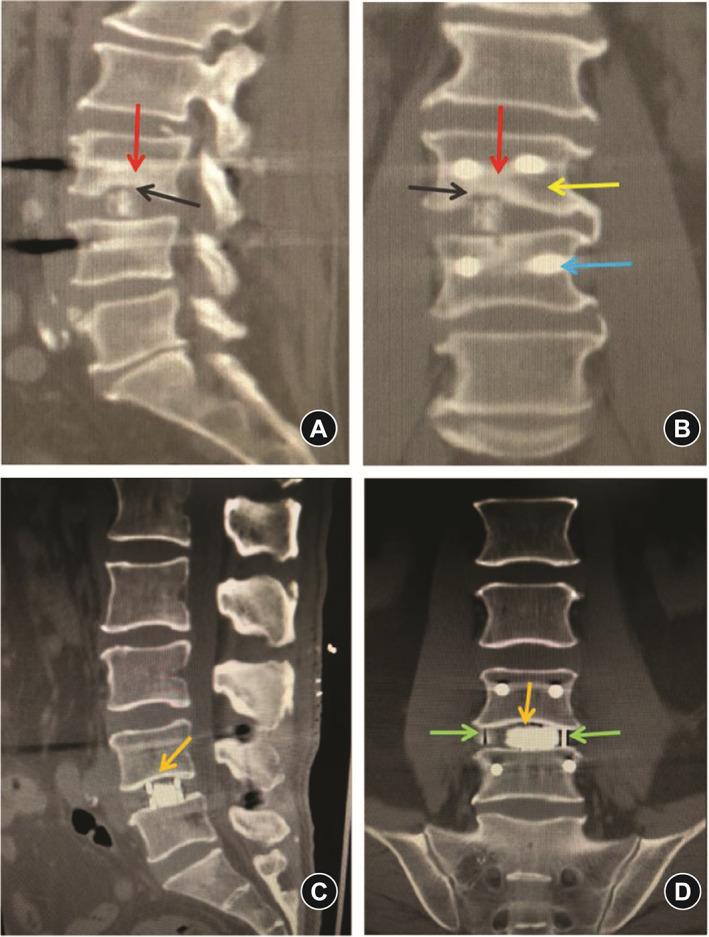

Based on the inclusion and exclusion criteria, the comparative analysis included consecutive patients with grade-1 degenerative spondylolisthesis who underwent oblique LIF (OLIF, n = 36) or minimally invasive transforaminal LIF (MI-TLIF, n = 45) at the Department of Spine Surgery, Beijing Jishuitan Hospital from January 2016 to August 2017. Patient satisfaction Japanese Orthopaedic Association score, visual analog scale (VAS) scores for back and leg pain, Oswestry disability index (ODI), radiographic outcomes including anterior/posterior disc heights (ADH/PDH), foraminal height (FH), foraminal width (FW), cage subsidence, cage retropulsion, and fusion rate were assessed during a 2-year follow-up. Continuous data are presented as mean ± standard deviation and were compared between groups using the independent sample t-test. Categorical data are presented as n (%) and were compared between groups using the Pearson chi-squared test or Fisher's exact test. Repetitive measurement and analysis of variance was employed in the analysis of ODI, back pain VAS score, and leg pain VAS score. Statistical significance was defined as p < 0.05.

The OLIF and MI-TLIF groups comprised 36 patients (age, 52.1 ± 7.2 years; 27 women) and 45 patients (age, 48.4 ± 14.4 years; 24 women), respectively. Satisfaction rates at 2 years post procedure exceeded 90% in both groups. The OLIF group had less intraoperative blood loss (140 ± 36 vs 233 ± 62 mL), lower back pain VAS score (2.42 ± 0.81 vs 3.38 ± 0.47), and ODI score (20.47 ± 2.53 vs 27.31 ± 3.71) at 3 months follow-up (with trends toward lower values at 2 years follow-up), but higher leg pain VAS scores at all postoperative time points than the MI-TLIF group (all p < 0.001). ADH, PDH, FD, and FW improved in both groups post-surgery. At the 2 year follow-up, the OLIF group had a higher rate of Bridwell grade-I fusion (100% vs 88.9%, p = 0.046) and lower incidences of cage subsidence (8.33% vs 46.67%, p < 0.001) and retropulsion (0% vs 6.67%, p = 0.046) than the MI-TLIF group.

OLIF 组和 MI-TLIF 组分别包括 36 例患者(年龄 52.1±7.2 岁,27 例女性)和 45 例患者(年龄 48.4±14.4 岁,24 例女性)。两组术后 2 年的满意度均超过 90%。OLIF 组术中出血量较少(140±36 比 233±62 mL),术后 3 个月时腰痛 VAS 评分(2.42±0.81 比 3.38±0.47)和 ODI 评分(20.47±2.53 比 27.31±3.71)较低(术后 2 年呈下降趋势),但术后各时间点腿痛 VAS 评分均高于 MI-TLIF 组(均 p<0.001)。两组术后 ADH、PDH、FD 和 FW 均得到改善。术后 2 年时,OLIF 组 Bridwell 分级融合率较高(100%比 88.9%,p=0.046),cage 下沉率较低(8.33%比 46.67%,p<0.001)和后移率较低(0%比 6.67%,p=0.046)。